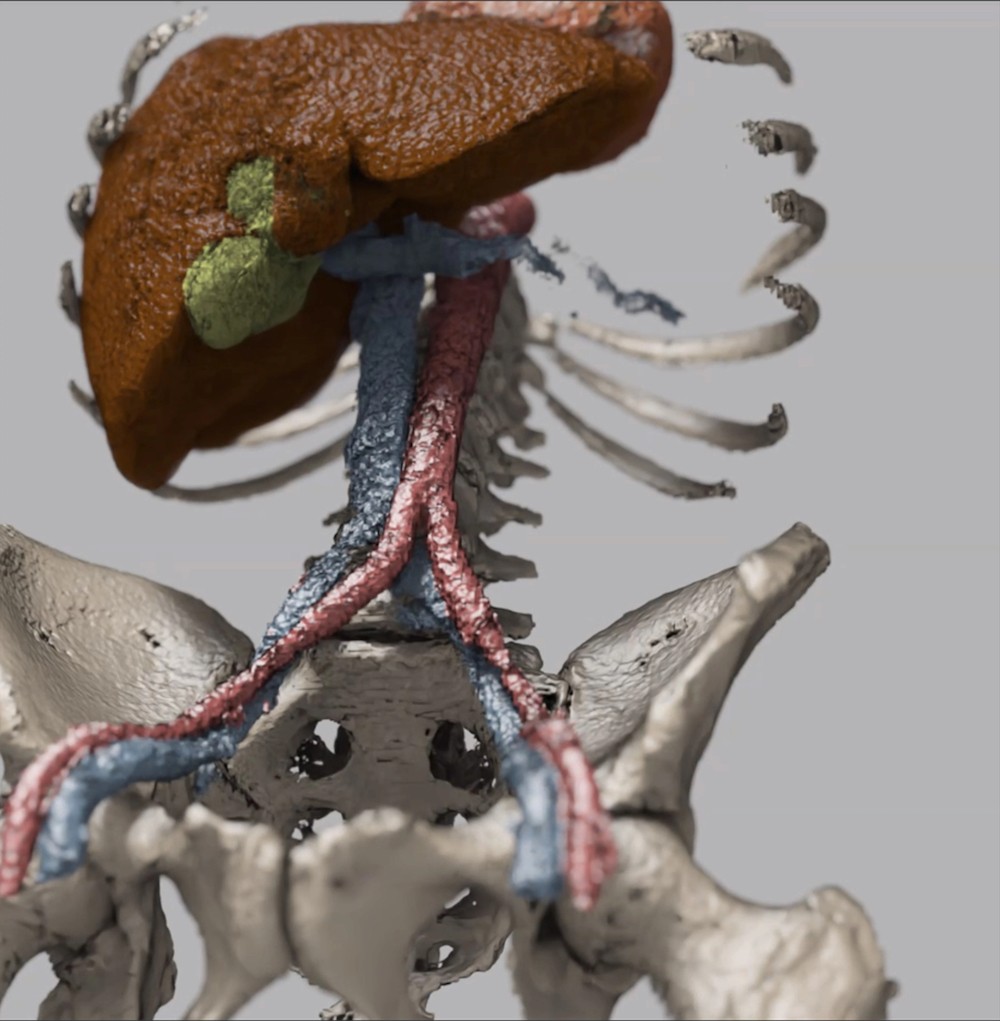

nvidia

vista-3d

VISTA-3D是一种专门的互动基础模型,用于分解和注解人类解剖。